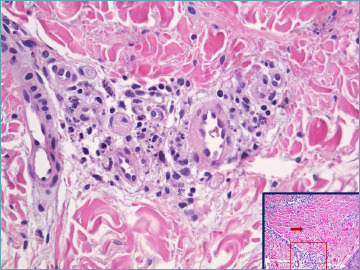

The mechanisms underlying the onset and progression of vasculitis remain poorly understood. This condition is characterized by damage to the vascular wall, recruitment of inflammatory cells, and subsequent structural remodeling, which are hallmarks of vasculitis. The histopathological classification of vasculitis relies on the size of the affected vessel and the predominant type of inflammatory cell involved - neutrophils in acute cases, lymphocytes in chronic conditions, and histiocytes in granulomatous forms. Pathological changes progress in every context, and a single vasculitic pattern can be associated with various systemic conditions. Conversely, a single causative agent may lead to multiple distinct clinical and pathological manifestations of vasculitis. Moreover, many cases of vasculitis have no identifiable cause. A foundational understanding of the normal structure of the cutaneous vascular network is crucial. Similarly, identifying the cellular and molecular participants and their roles in forming the "dermal microvascular unit" is propedeutical.

This review aims to elucidate the complex mechanisms involved in the initiation and progression of vasculitis, offering a comprehensive overview of its histopathological classification, underlying causes, and the significant role of the cutaneous vascular network and cellular dynamics. By integrating the latest insights from studies on NETosis and the implications of lymphocytic infiltration in autoimmune diseases, we seek to bridge gaps in current knowledge and highlight areas for future research. Our discussion extends to the clinical implications of vasculitis, emphasizing the importance of identifying etiological agents and understanding the diverse histopathological manifestations to improve diagnostic accuracy and treatment outcomes.